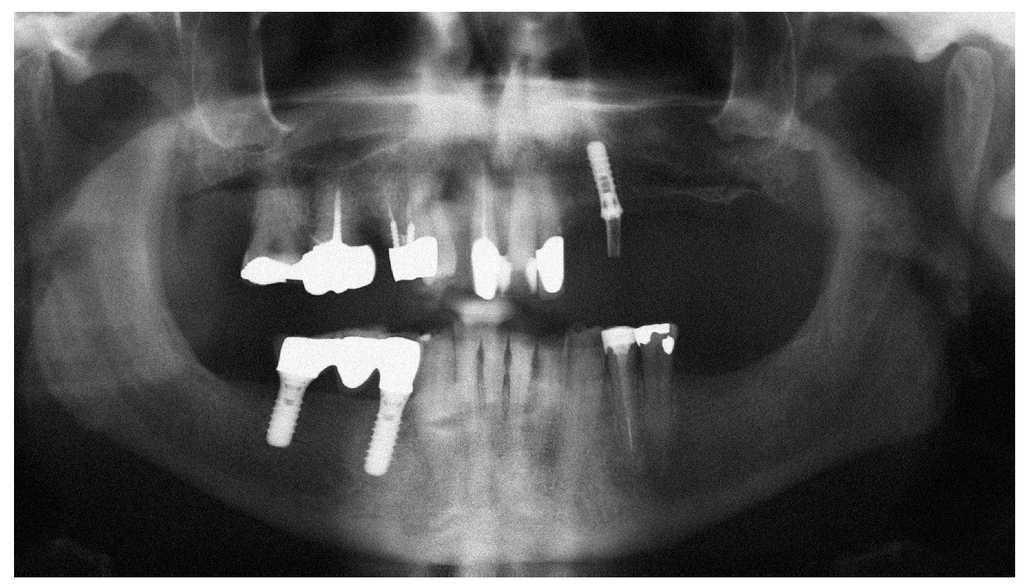

Figura 2a. Radiografía panorámica de un paciente de 69 años sometido a tratamiento con bifosfonatos intravenosos (Zometa) y a tratamiento concomitante con corticosteroides (ambos desde 2004) por un carcinoma de próstata metastatizado. En diciembre de 2006 le fue exodonciado el diente 37 por el odontólogo de cabecera. El paciente fue remitido a nuestra clínica en junio de 2007 por una falta de cicatrización del alvéolo varios meses después de la intervención.

Figura 3a. Radiografía panorámica de una paciente de 68 años con un carcinoma de mama con metástasis óseas. Desde el año 2002 la paciente es tratada periódicamente con bifosfonatos intravenosos (Aredia). En 2006, el odontólogo de la paciente extrajo parte de los dientes de la mandíbula y la totalidad de los dientes superiores. La curación evolucionó de forma tórpida, sobre todo en la mandíbula, y provocó precozmente una dehiscencia de tejidos blandos. Así y todo, esta paciente no nos fue remitida hasta al cabo de 1 año.

Figura 4a. Radiografía panorámica de un paciente de 64 años con carcinoma de próstata metastatizado. El paciente recibe tratamiento con bifosfonatos intravenosos (Zometa) desde 2005. El paciente es portador de una prótesis total desde hace varios años. En junio de 2007 experimentó una sensación de presión debajo de la prótesis en la región mandibular izquierda, que no desapareció después de varios intentos de ajuste por el protésico dental. En julio de 2007, el odontólogo de cabecera remitió al paciente al servicio de urgencias de nuestra clínica.